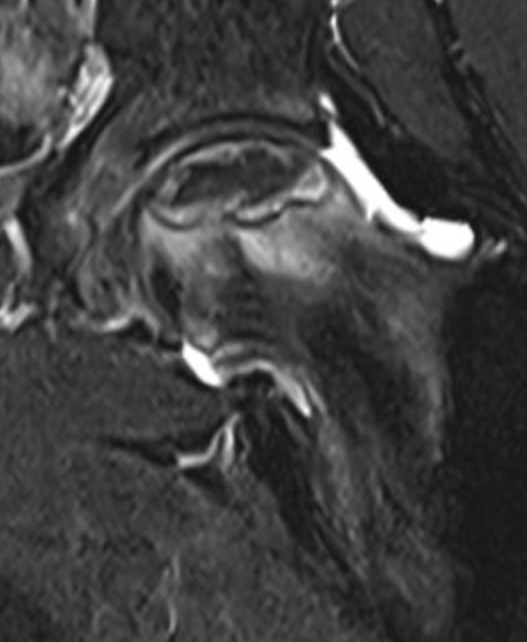

Core Decompression

Concept

Theory

- decompress intraosseous hypertension

- promote revascularization

Arthroscopic multiple small drill holes techniques

- hip arthroscopy

- central compartment

- identify head neck junction

- multiple 1.5 mm drill holes into lesion in femoral head

- +/- BMAC